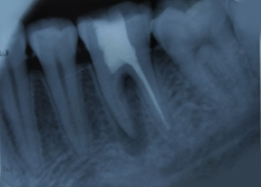

Pre-OP IOPAR